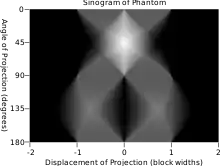

En el contexto de las tomografías la transformada de Radon se le suele llamar senograma puesto que la transformada de Radon de una función delta tiene como respuesta característica un seno. En consecuencia, la representación gráfica de la transformada de Radon de un conjunto de pequeños objetos parece una colección de senos con diferentes fases y amplitudes.

| Fantasma de Shepp-Logan; Transformada de Radon; y Transformada de Radon inversa | ||

lo que significa que la imagen original puede ser recuperada del 'sinograma' aplicando un filtro rampa (sobre la variable ) y entonces retroproyectando. Como que el paso de filtrado puede ser implementado de forma eficiente (mediante técnicas de procesamiento digital de señales) y la retroproyección no es más que una acumulación de valores en los píxeles de la imagen, resulta un algoritmo altamente eficiente, por lo que se trata de un algoritmo ampliamente usado.